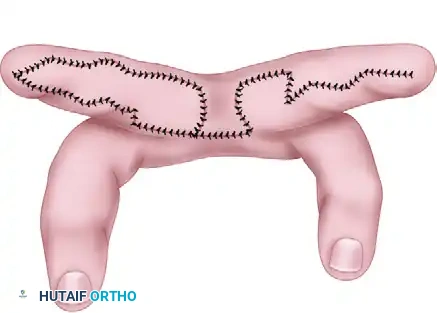

BIOMECHANICS OF THE Z-PLASTY IN RING SYNDROME

Simple excision of a congenital groove with a direct, everting closure is universally condemned in modern operative orthopedics. A linear, circumferential incision will inevitably heal with a circumferential scar. As this scar matures and contracts, it will recreate the exact tourniquet effect the surgery was intended to cure.

The multiple Z-plasty technique is the gold standard. A Z-plasty serves two critical biomechanical functions:

1. Elongation: By transposing two triangular flaps, the central limb of the Z is elongated. A classic 60-degree Z-plasty increases the length of the tissue in the direction of the central limb by approximately 73%.

2. Redirection of Scar Tension: The Z-plasty breaks up the linear scar, redirecting the forces of scar contracture by 90 degrees, thereby completely eliminating the risk of a recurrent circumferential stricture.

Flap Elevation and Transposition:

- Sharply incise the limbs of the Z-plasties to create the triangular flaps.

- Elevate the flaps at the level of the deep subcutaneous tissue, ensuring a robust subdermal plexus is maintained to prevent tip necrosis.

- Transpose the flaps in an interdigitating fashion. This maneuver will immediately release the constriction and visibly lengthen the segment.

Closure and Hemostasis:

- Deflate the tourniquet before final closure to ensure meticulous hemostasis. Bipolar electrocautery should be used sparingly to avoid thermal injury to the delicate pediatric skin edges.

- Suture the flaps using fine, absorbable sutures (e.g., 5-0 or 6-0 chromic gut or fast-absorbing plain gut) to avoid the need for suture removal in an awake infant. Place deep dermal interrupted sutures to take tension off the epidermal closure.